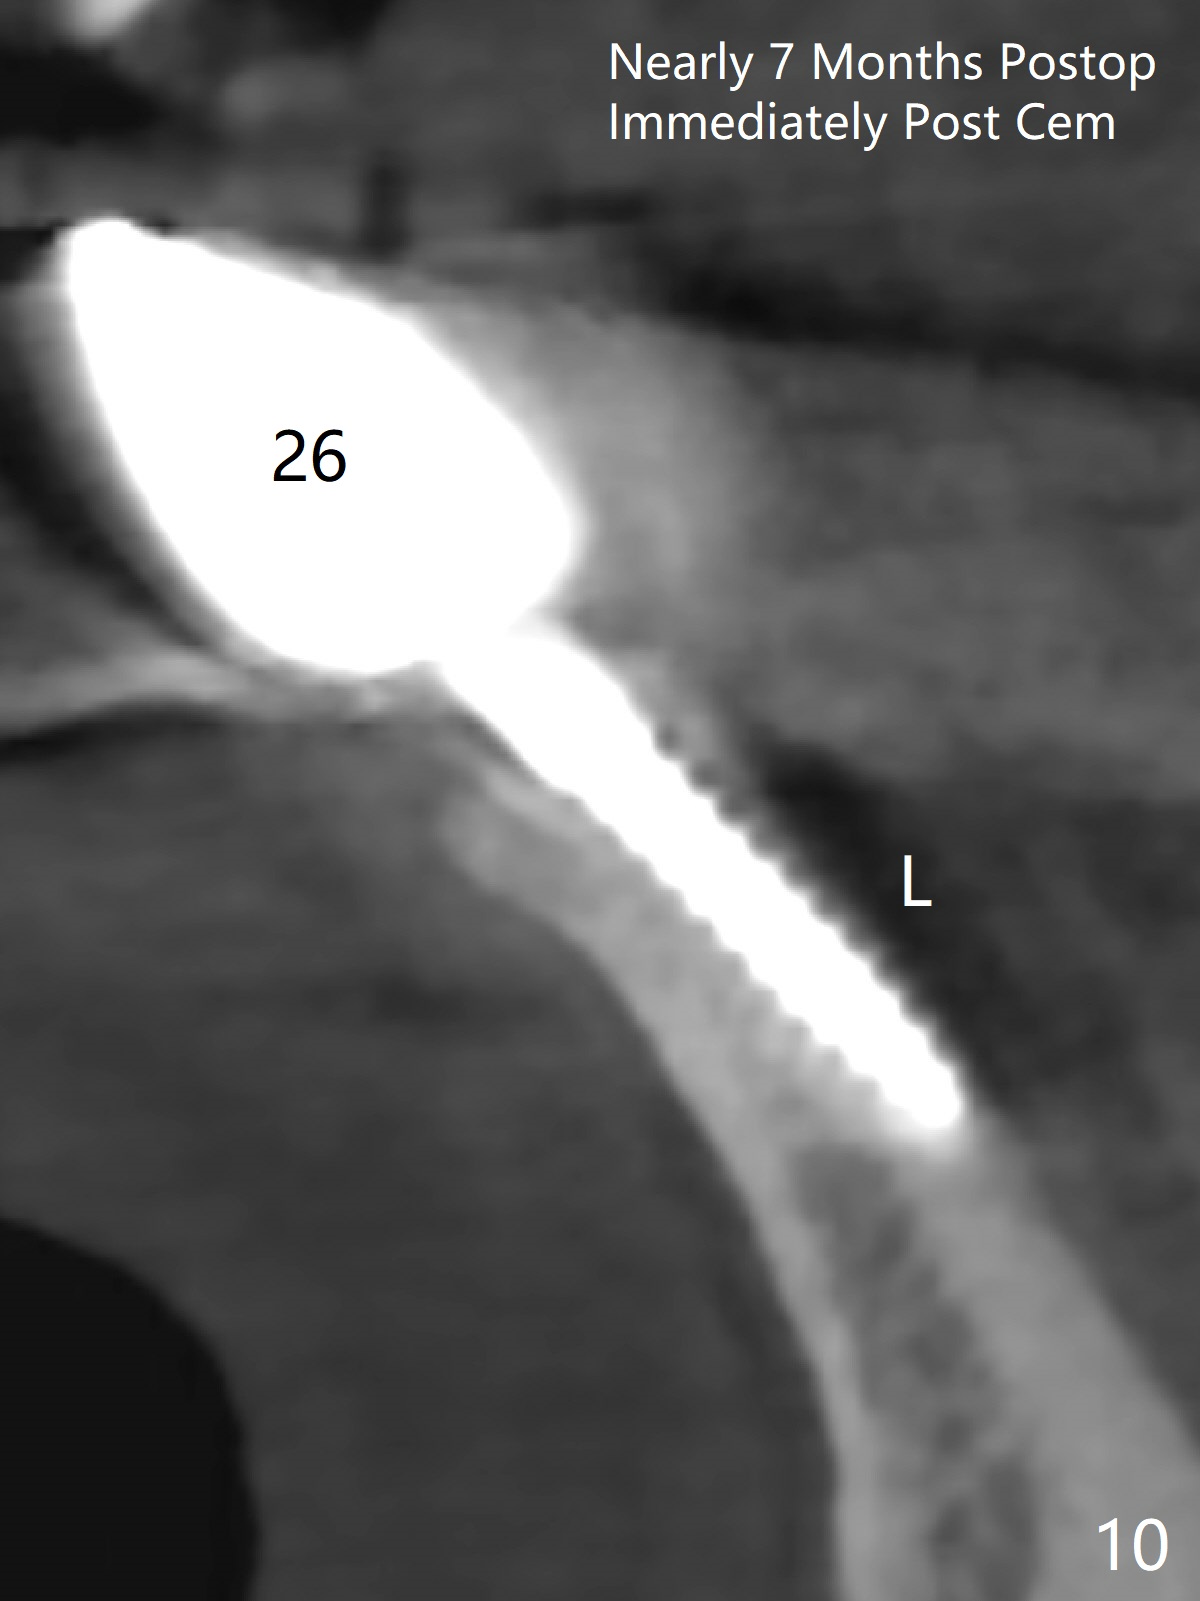

When the patient returns, the tooth #24 has exfoliated, while the ones at #25 and 26 has mobility III (Fig.1). The patient requests the tooth #23 extraction (Fig.2), but not #27. After SRP and extraction, osteotomy is initiated mesial to the sockets #23,25 and 26 (Fig.3,4) with intention to place 3 1-piece implants for 3 incisor crowns (Fig.5,6). Following Vanilla graft (Fig.5 *) a splinted provisional is fabricated to close the sockets (Fig.6). Peri-implant spaces close 5.5 months postop (Fig.7). Impression is taken after reprep for margin and parallelism (Fig.8). The final restoration consists of #23 single unit crown and #24-26 3-unit FPD (Fig.9). It appears that 2.5 mm 1-piece implants are not too small for the lower incisors (Fig.10-12), especially the central one (Fig.11). There may be perforation in the apical half of the lingual plate (L in Fig.10). The patient is not pleased with the shade of the #24-26 3-unit FPD (Fig.13 (6 months post cementation)). There is metal show through the abutments (*).